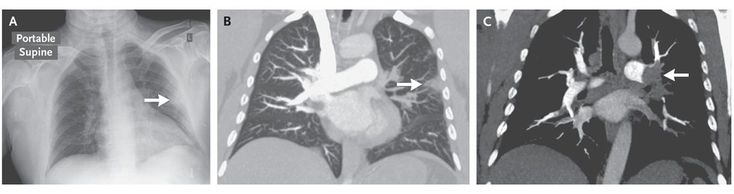

A 46-year-old man presented to the emergency department with the sudden onset of dyspnea, pleuritic chest pain, and hypoxemia. The patient's medical history and family history were unremarkable. An electrocardiogram showed a deep S wave in lead I, a large Q wave in lead III, an inverted T wave in lead III, and an incomplete right bundle-branch block, suggesting right ventricular strain. The patient underwent chest radiography, which revealed a Hampton's hump on the left side of the chest (Panel A, arrow). Computed tomographic pulmonary angiography further defined this area of pulmonary infarction (Panel B, arrow) and revealed bilateral pulmonary emboli, including a thrombus in the left main pulmonary artery (Panel C, arrow). Originally described in 1940 by Hampton and Castleman, Hampton's hump is a peripheral wedge-shaped opacification abutting the pleura, signifying pulmonary infarction distal to a pulmonary embolism. The majority of pulmonary emboli do not result in infarction of the distal lung, presumably because of vascular collateralization. Infarction is most likely to occur in patients with large pulmonary emboli or underlying lung disease. Anticoagulation therapy was initiated, and the patient was discharged home in stable condition.